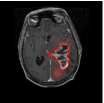

The relevance of tumor shape in characterizing tumor heterogeneity is linked to its growth process. Intrinsic brain tumors tend to evolve along tracts of white matter, altering the tracts in complex ways that include infiltration, displacement and disruption (Goldberg-Zimring et al., 2005). It is conceivable that new insight into patterns of tumor growth and invasion in the brain can be obtained through a better understanding of the shape and evolution of the tumor. Tumor shape is significantly influenced by the location in the brain and other anatomical constraints—in some places it might infiltrate and in others displace the fiber tracts. Irregular or spiculated shapes suggest an anisotropic structure of the underlying white matter; spherical or regular shapes imply a lack of structural or anatomical restrictions. The size of the tumor evidently affects its shape, especially in the presence of anatomical restrictions. It is reasonable to theorize that a better understanding of the relationship between the tumor’s shape and size, and histopathological factors related to the brain tumor would enhance the understanding of the tumor’s biological growth process; this would not only enable better prognosis but also potentially predict the likelihood of therapeutic success. For example, Figure 1 of our motivating dataset shows two semi-automated segmentations of T2-weighted fluid-attenuated inversion recovery (FLAIR) brain-axial MRI of patients diagnosed with glioblastoma multiforme (GBM), also known as grade IV glioma, with survival times of longer than 50 months (left) and shorter than one month (right), respectively. The tumor shape for the patient with longer survival appears to be more regular or spherical than the irregular one corresponding to the patient with a short survival; the tumor sizes appear to be quite different as well. Evidently, the tumor locations for the two patients are different, which influences both size and shape.

![]() |